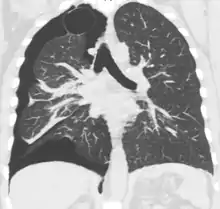

الأشعة المقطعية

التصوير المقطعي بالكمبيوتر ليس ضروريا لتشخيص استرواح الصدر، ولكن يمكن أن يكون مفيدا في حالات معينة. في بعض أمراض الرئة، وخاصة انتفاخ الرئة، يمكن أن يوجد مناطق من الرئة غير طبيعية مثل وجود فقاعات (كيس كبير مملوء بالهواء) يكون لها نفس مظهر استرواح الصدر بالأشعة السينية على الصدر، وقد لا يكون آمنا تطبيق أي علاج قبل القيام بالتمييز، وتحديد الموقع الدقيق، وحجم استرواح الصدر.[13] في حالة الخبطات أو الطعنات، قد لا يكون من الممكن إجراء فيلم في الوضع القائم، وقد لا يتمكن التصوير الشعاعي للصدر من تصوير ما يصل إلى ثلث استرواح الصدر، لذا يكون التصوير المقطعي بالكمبيوتر هو الأفضل في هذه الحالة.[16]

وهناك استخدام آخر للأشعة المقطعية هو في تحديد أي أمراض أخرى كامنة في الرئتين. حيث يمكن أن يساعد على تحديد البثور أو الأمراض الكيسية (تحسبا للعلاج، انظر أدناه) في حالة استرواح الصدر الأولي، كما يمكن أن يساعد على تحديد معظم الأسباب المذكورة أعلاه في حالة استرواح الصدر الثانوي.[13][17]